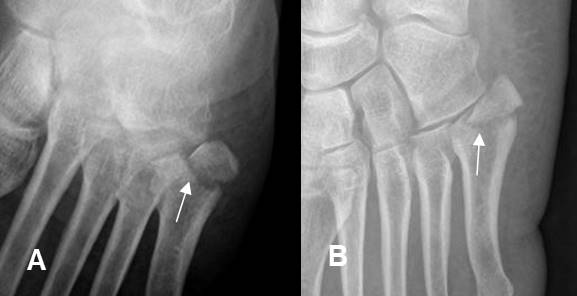

Fig 170. Fractura del bailarín.

A: Rx AP y B: Rx oblicua del pie. Fractura desplazada y con compromiso intra-articular, en la base del 5º metatarsiano, por avulsión del peroneo corto.